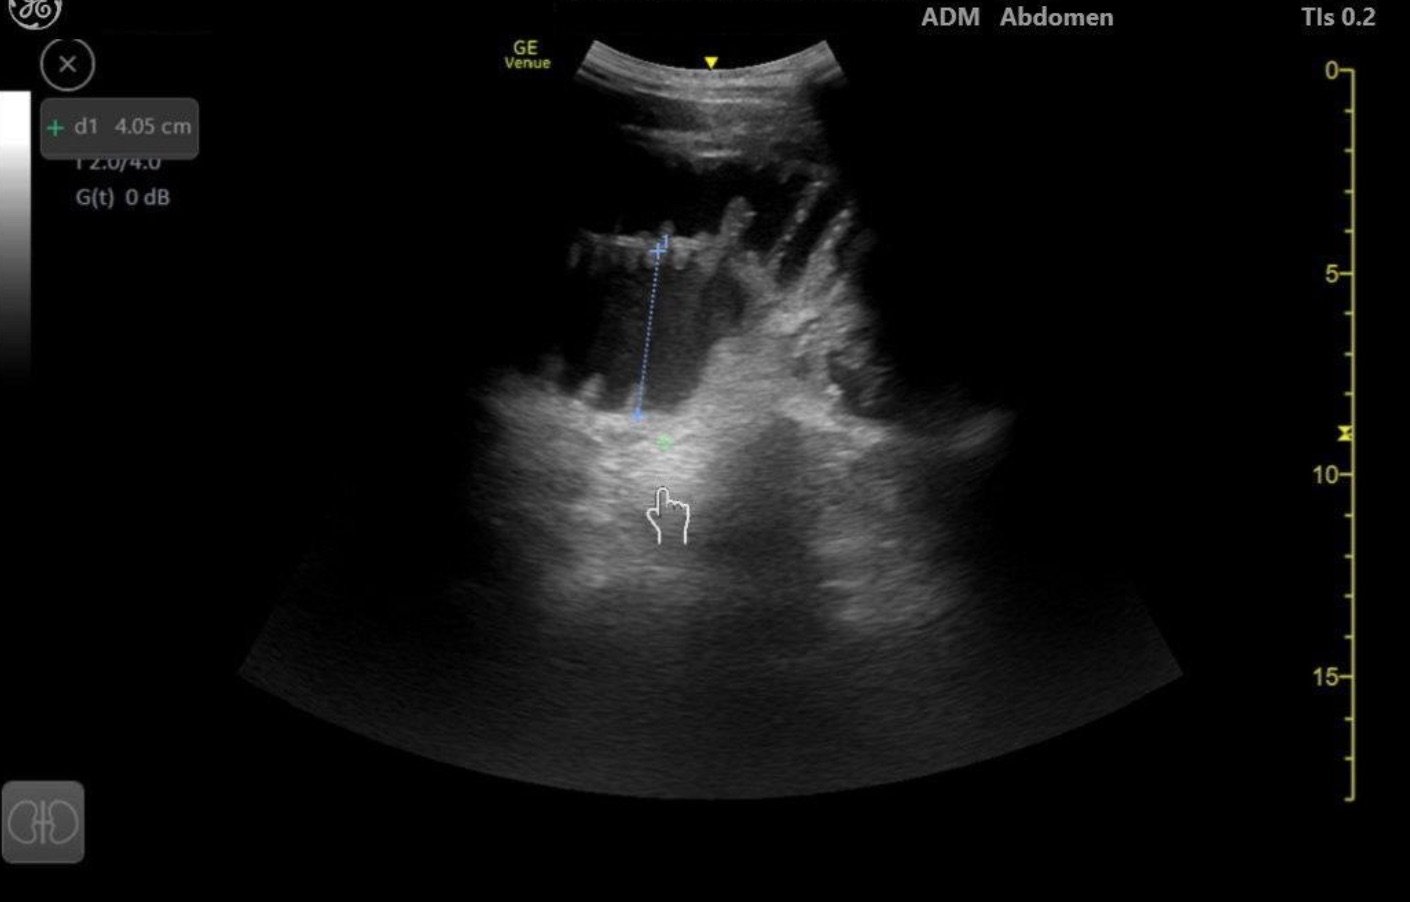

Brief narrative description of case

75 year old male with PMH of HTN, HLD presenting with concern of right sided abdominal pain for 3 days, progressively worsening. He appears uncomfortable and is tachycardic on arrival. The goals for this case are to recognize the differential diagnosis and the role of using bedside POCUS to diagnose and expedite care.